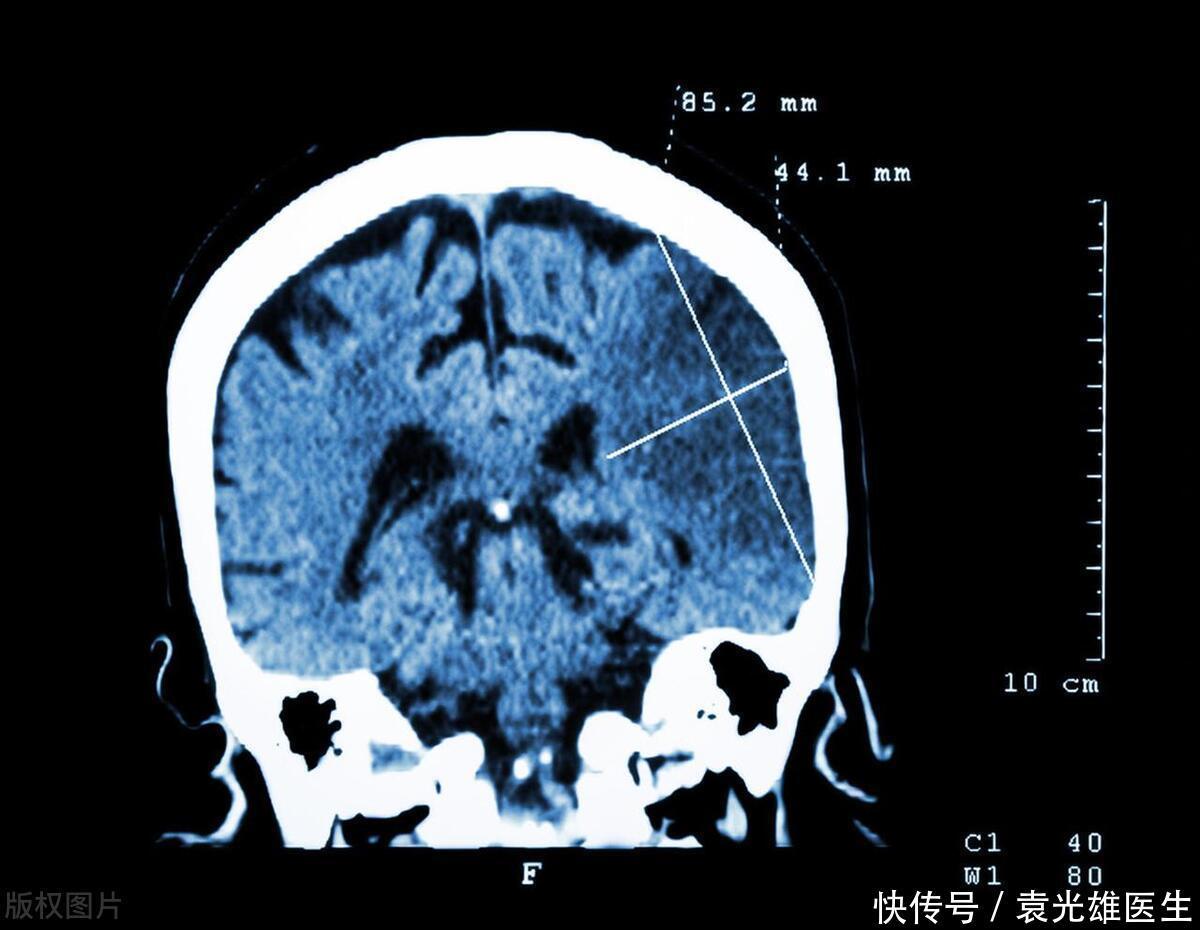

脑梗并非突然来袭,病发前几个月,身体会有 6 种异常,需警惕

脑梗,就像是一场悄然潜伏的风暴,在人们毫无防备之时,可能会突然爆发带来巨大的危害。但其实,脑梗并非突然来袭,在病发前的几个月,身体往往会发出一些信号,如同黑暗中的点点微光,提醒着我们要提高警惕。